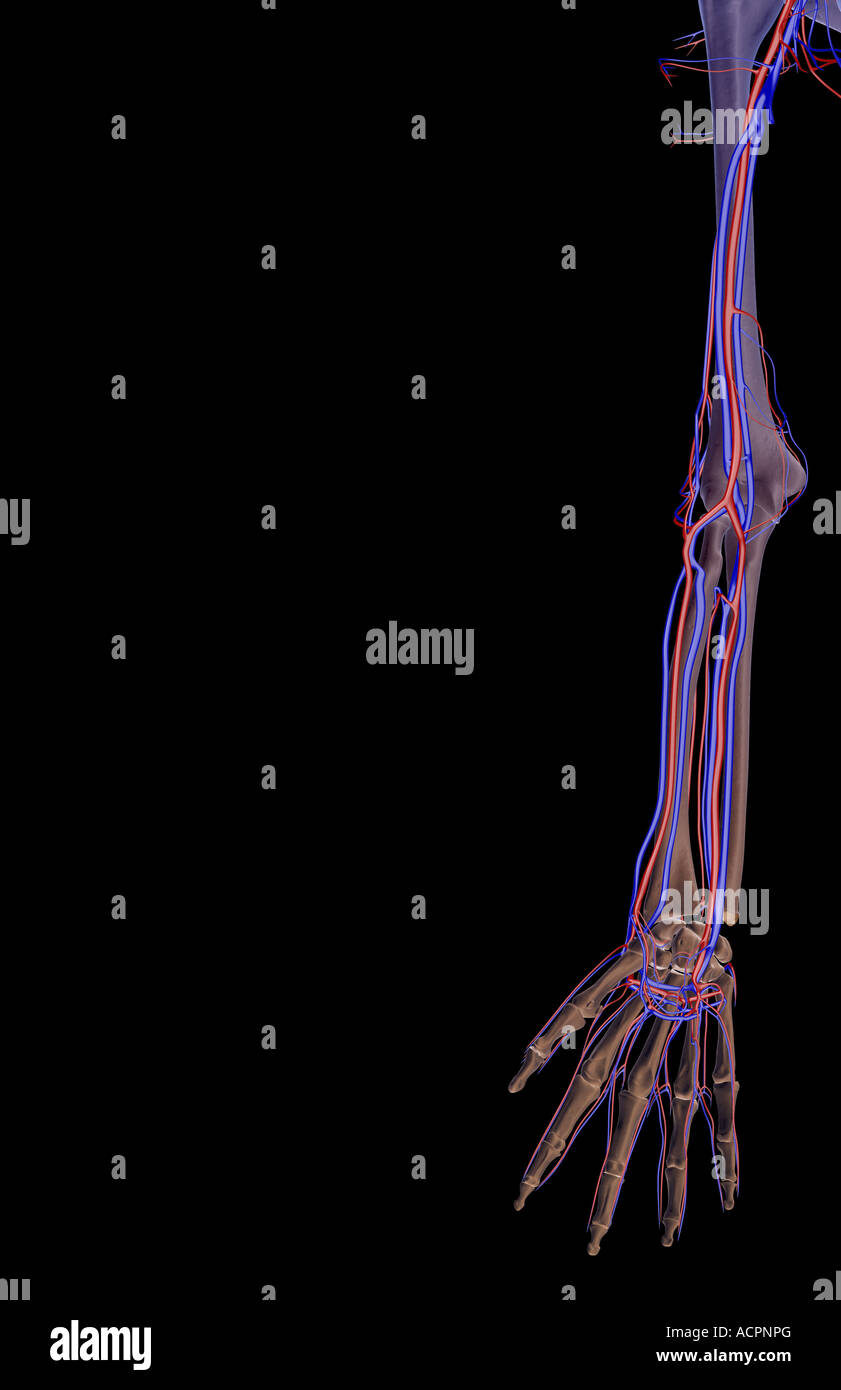

The blood supply of the upper limb Stock Photohttps://www.alamy.com/image-license-details/?v=1https://www.alamy.com/stock-photo-the-blood-supply-of-the-upper-limb-13209879.html

The blood supply of the upper limb Stock Photohttps://www.alamy.com/image-license-details/?v=1https://www.alamy.com/stock-photo-the-blood-supply-of-the-upper-limb-13209879.htmlRFACPNPG–The blood supply of the upper limb